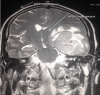

IRM cérébrale, séquence T1 avec injection de gadolinium: volumineux processus tumoral gauche entrant en contact avec la dure mère associé à un œdème péri-lésionnel et un effet de masse